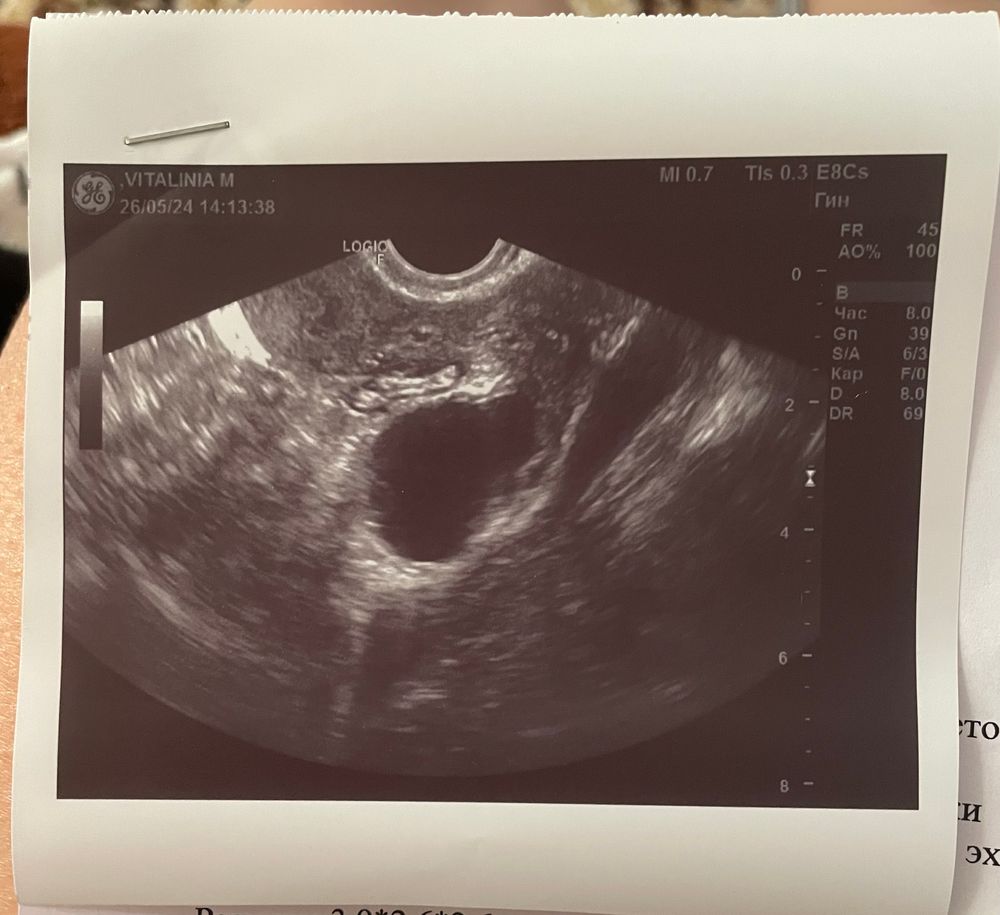

Была ли овуляция?

Да эндометрий тонковат его нижняя граница 8 мм для зачатия надо 10 мм- 12 как минимум

Судя по второму узи да, если врач правильно определил, что это кистозное ЖТ. Ну и плюс жидкость есть, жидкость плюс ЖТ говорит о том, что вот вот вчера-позавчера была О. Но у вас эндометрий тонковат